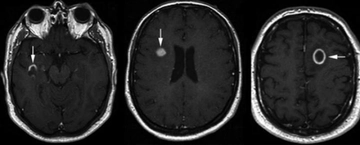

Kafa içindeki lezyonlar, çeşitli nedenlerle oluşabilen anormal doku büyümeleri veya hasarlarıdır. Bu lezyonlar, beyin dokusunda, meninkslerde veya kafatasının diğer bölgelerinde gelişebilir. Lezyonların varlığı, çeşitli belirtilerle kendini gösterebilir ve bu belirtiler, lezyonun türüne, boyutuna ve bulunduğu yere bağlı olarak değişiklik gösterebilir. Lezyon TürleriKafa içindeki lezyonlar, genel olarak birkaç ana kategoriye ayrılabilir:

Tanı YöntemleriKafa içindeki lezyonların tanısı, genellikle hem klinik muayene hem de görüntüleme yöntemleri ile konulur. Kullanılan başlıca yöntemler şunlardır: